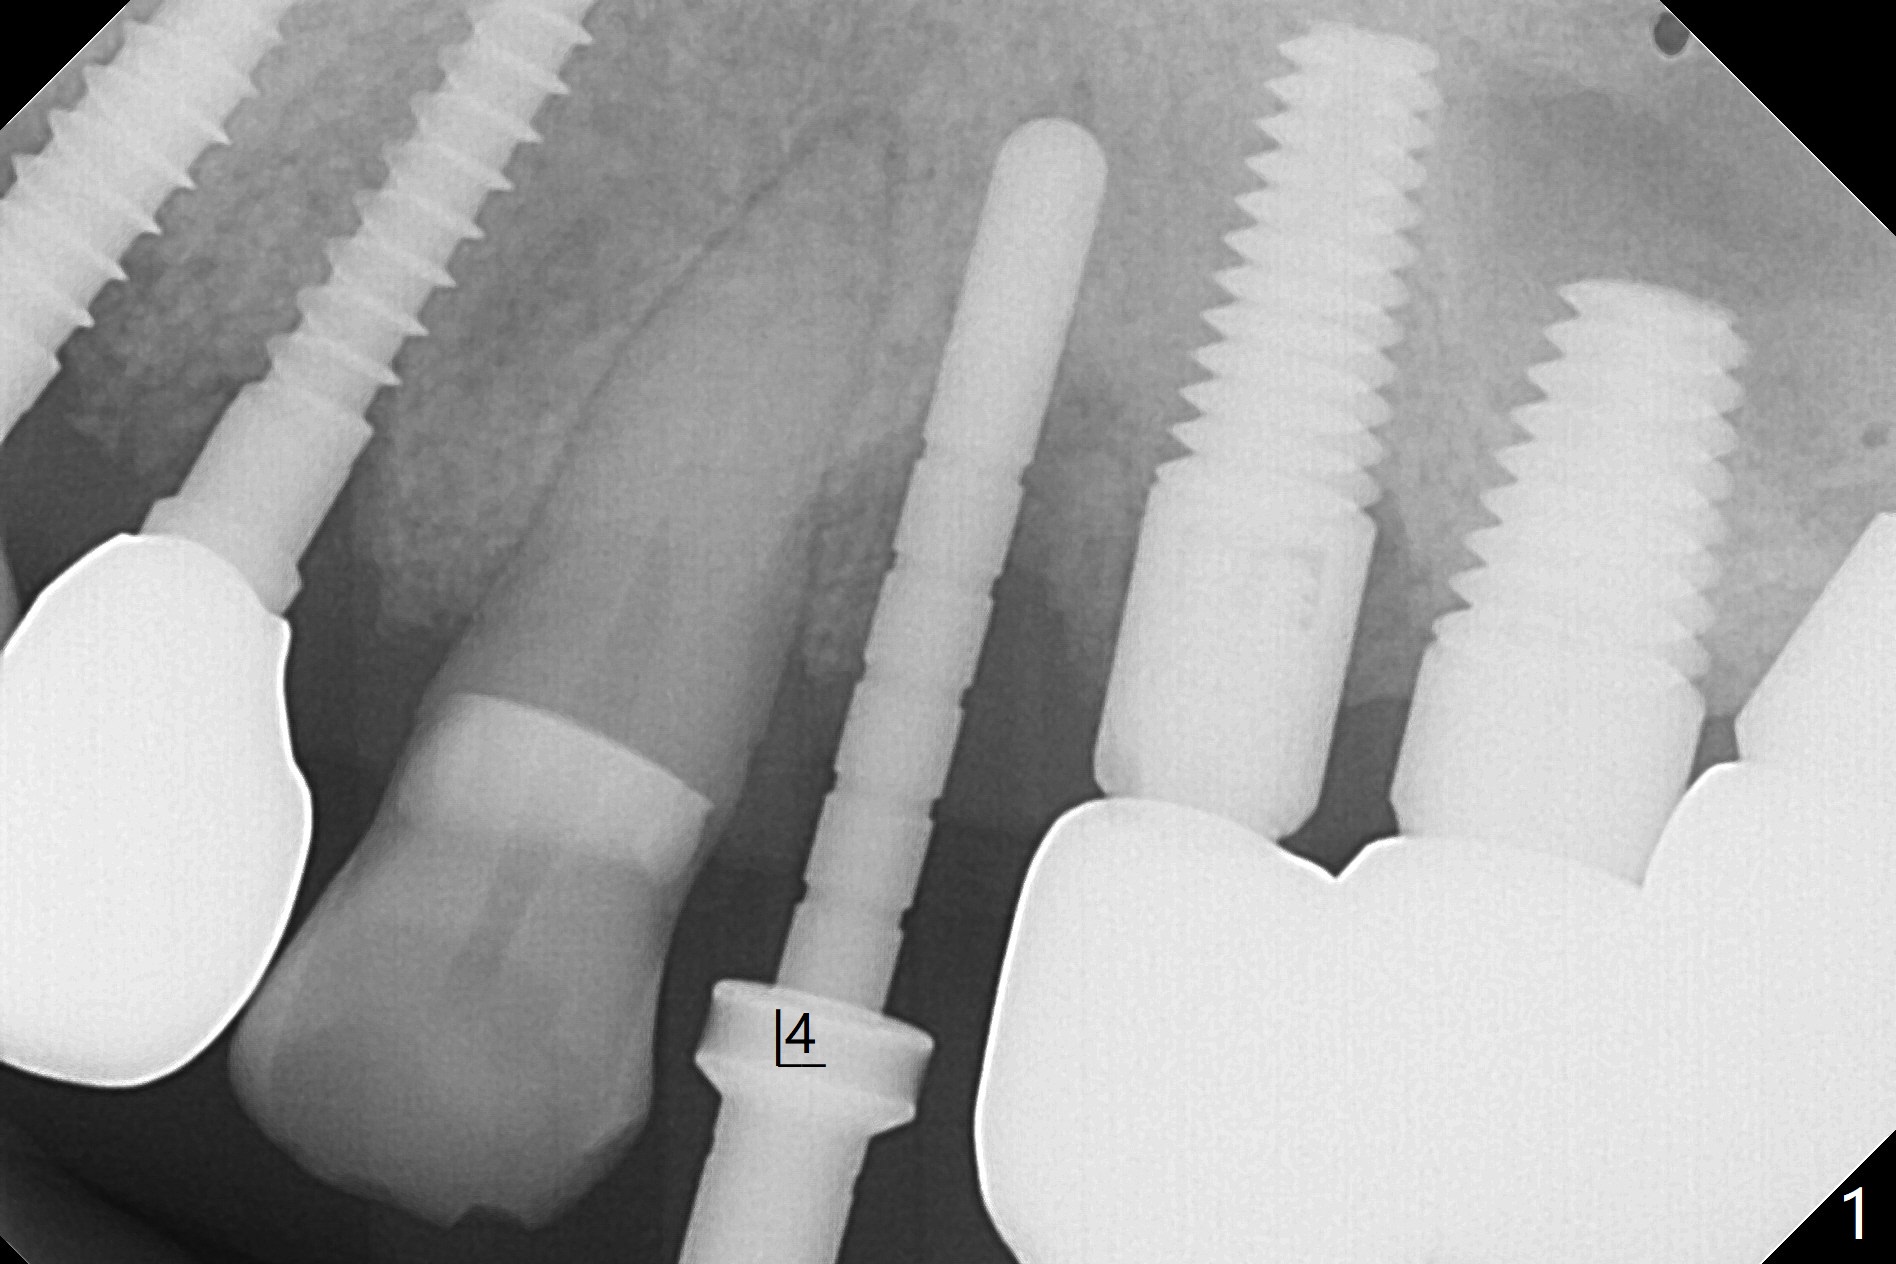

66岁男士口腔卫生好,但是许多牙齿可能因为咀嚼力太大,骨质吸收而失去,包括左上四(没有颊侧骨板),拔除后2毫米钻头显示钻洞接近尖牙(图一),好像不容易改变钻洞位置,病人对手术恐惧,干脆植入一段式植体(图二,三)。植骨后(图二*),制备即刻临时牙冠。后者戴入前不小心颊侧边缘过度修正,就在原位添加树脂,两周后显得胖些(图四 *),远中形成倒凹,不容易取出,只好稍微修正。